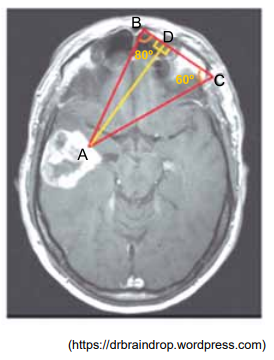

A imagem, obtida por tomografia computadorizada, revela a presença de um tumor cerebral no ponto A. O método de triangulação sobre essa imagem indica que as medidas dos ângulos e

são, respectivamente, 80° e 60°.

Adotando-se tg 60º = m, tg 80º = n e utilizando-se a medida de igual a ℓ, a distância do ponto A ao segmento de reta

, indicada na figura por

, será igual a